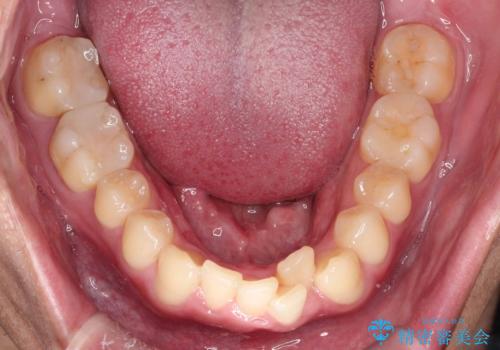

- 「上の前歯の捻じれと下の前歯のでこぼこを治したい」を主訴に来院された患者様です。

矯正検査の結果、非抜歯で矯正可能だったためインビザラインで治療を行いました。

アーチの拡大とIPRで叢生を改善いました。

11ヵ月で矯正を終える事ができ患者様も大変ご満足されていました。